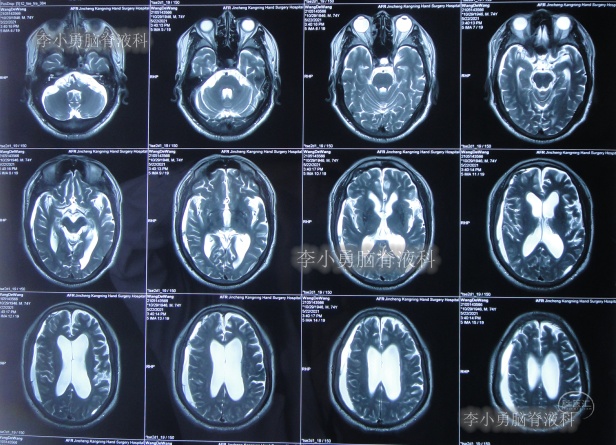

发现脑积水后8天即2020年11月6日,就诊于第2家的上海的某三甲医院,入院后再次检查(图-2)后诊断为正常压力脑积水。

图-2:2020年11月11日头部核磁